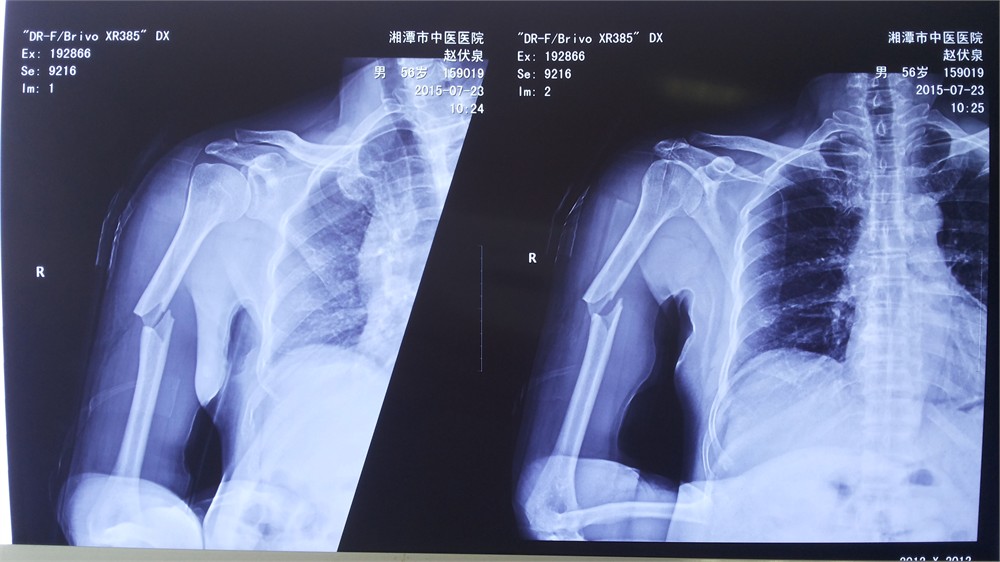

趙先生家住湘潭縣沙泉村,2015年7月底,在家摔倒致右上臂腫脹疼痛,活動(dòng)受限,來(lái)我院求治。X線片顯示:右肱骨中段骨折,斷端旋轉(zhuǎn)移位,向外后成角,骨折端有一蝶形骨片。對(duì)于這一類明顯移位并伴有旋轉(zhuǎn)的骨折,手法整復(fù)有一定的難度,而且在治療的過(guò)程中容易出現(xiàn)再次移位,現(xiàn)代醫(yī)學(xué)多主張手術(shù)治療,行切開復(fù)位鋼板內(nèi)固定。

“能不能不做手術(shù)?我是農(nóng)村的,家里經(jīng)濟(jì)條件不好,手術(shù)治療以后還要取鋼板,費(fèi)用負(fù)擔(dān)不起。”趙先生反復(fù)懇求醫(yī)生。湯智醫(yī)師接診了病人,予以了手法整復(fù)并夾板外固定。復(fù)查X線片見右肱骨骨折旋轉(zhuǎn)移位完全糾正,略向外側(cè)成角。如下圖: